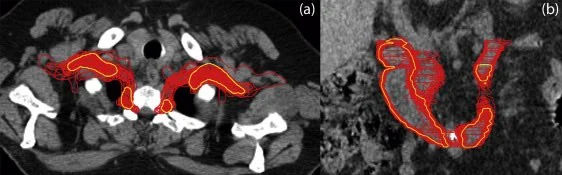

Title: Top 10 Tips for Stereotactic Body Radiation Therapy Contouring and Planning in Oligometastatic Disease: Lessons Learned From the UK SBRT QA Program

Authors: Patricia Díez, Emma M. Dunne, Rushil Patel, Christopher Dean, Sarah Osman, Fiona McDonald